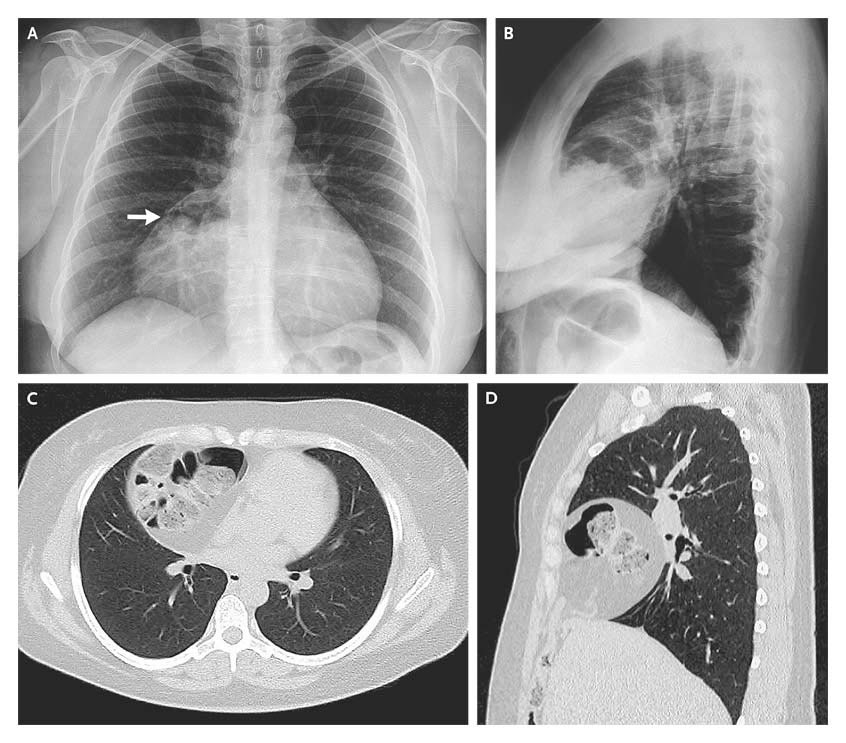

Lumbar hernia. (a) Axial computed tomography (CT) demonstrating Lumbar Hernia Radiology lumbar hernias occur through defects in the lumbar muscles or the posterior fascia, below the 12 th rib and above the iliac crest. Learn about disc herniation, facet arthrosis,. while several guidelines on clinical and neuroradiological diagnosis of herniated lumbar disc have been. a lumbar hernia refers to a protrusion of tissue through a defect in the. Lumbar Hernia Radiology.